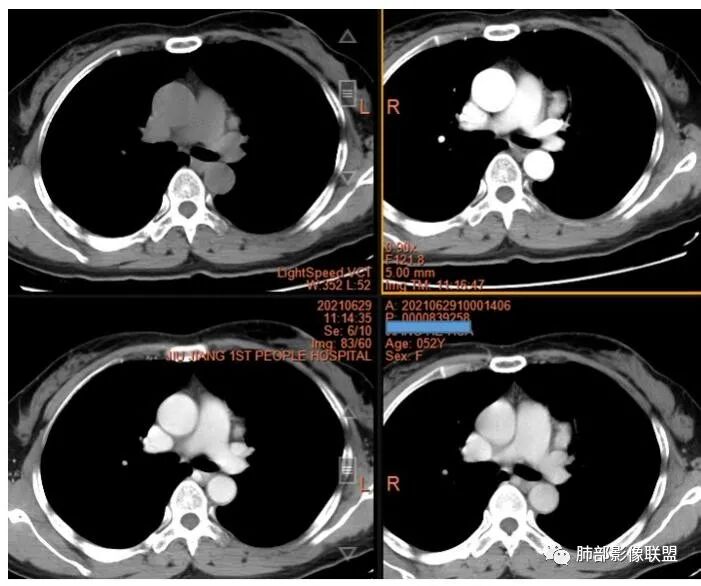

2.左上纵隔肺门夹角处孤立实性密度结节影,边界清楚浅分叶,密度均匀,未见液化、分隔及钙化。

3.动脉期起显著强化并延续至静脉期,强化程度均低于同期胸主动脉。病灶弧形推压左上肺动脉,毗邻左肺上叶支气管但未见侵蚀及突入,相应支气管未见狭窄。

2.富血供应当想到副节瘤。应当结合临床表现,有无高血压,尿甲氧基肾上腺素水平或血浆儿茶酚胺的实验室数据等等。

3.血管瘤(如海绵状血管瘤)可以显著强化,但常为渐进性强化,且软组织内血管瘤一般也没那么“抱团”。